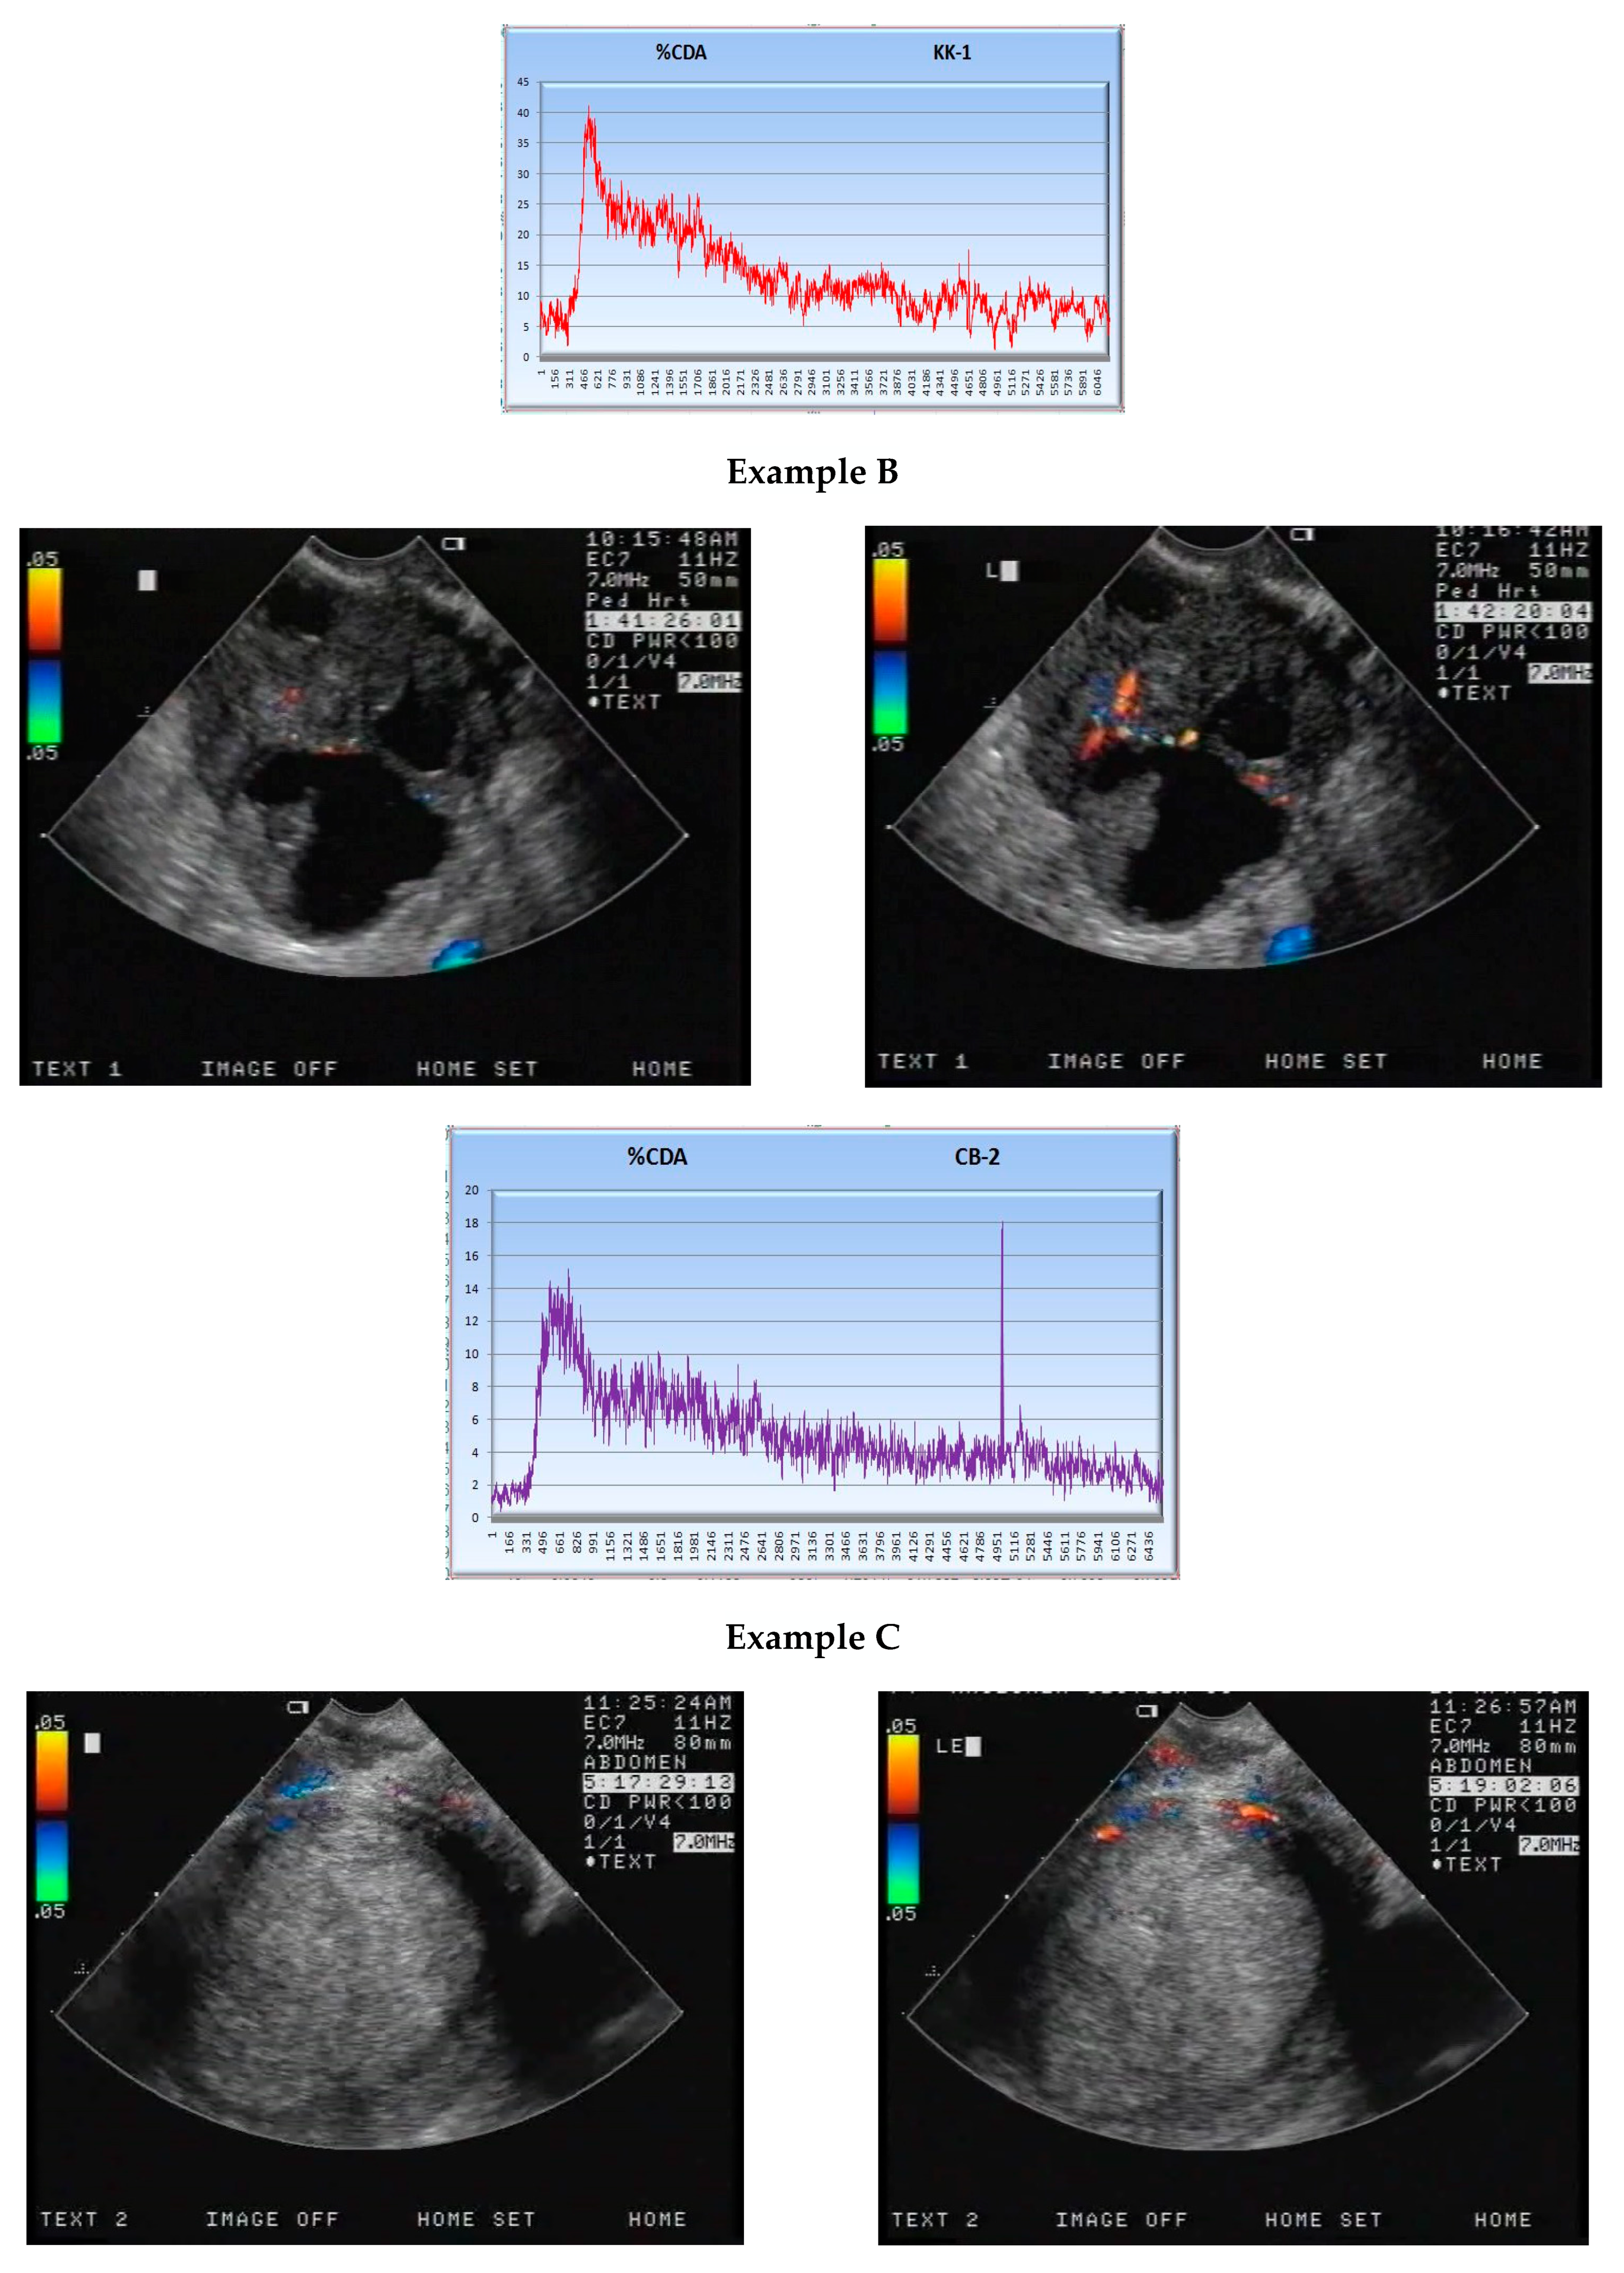

2.2. CEUS

3.1. S Parameter

3.2. Correlation of the S Parameter with CD34-, CD105- and BCL2-Expression Levels